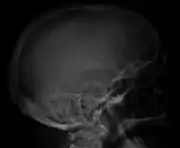

The diagnostic examination of a person with suspected multiple myeloma typically includes a skeletal survey. This is a series of X-rays of the skull, axial skeleton, and proximal long bones. Myeloma activity sometimes appears as "lytic lesions" (with local disappearance of normal bone due to resorption). And on the skull X-ray as "punched-out lesions" (raindrop skull). Lesions may also be sclerotic, which is seen as radiodense.[59] Overall, the radiodensity of myeloma is between −30 and 120 Hounsfield units (HU).[60] Magnetic resonance imaging is more sensitive than simple X-rays in the detection of lytic lesions, and may supersede a skeletal survey, especially when vertebral disease is suspected. Occasionally, a CT scan is performed to measure the size of soft-tissue plasmacytomas. Bone scans are typically not of any additional value in the workup of people with myeloma (no new bone formation; lytic lesions not well visualized on bone scan).

Skull X-ray showing multiple lucencies due to multiple myeloma